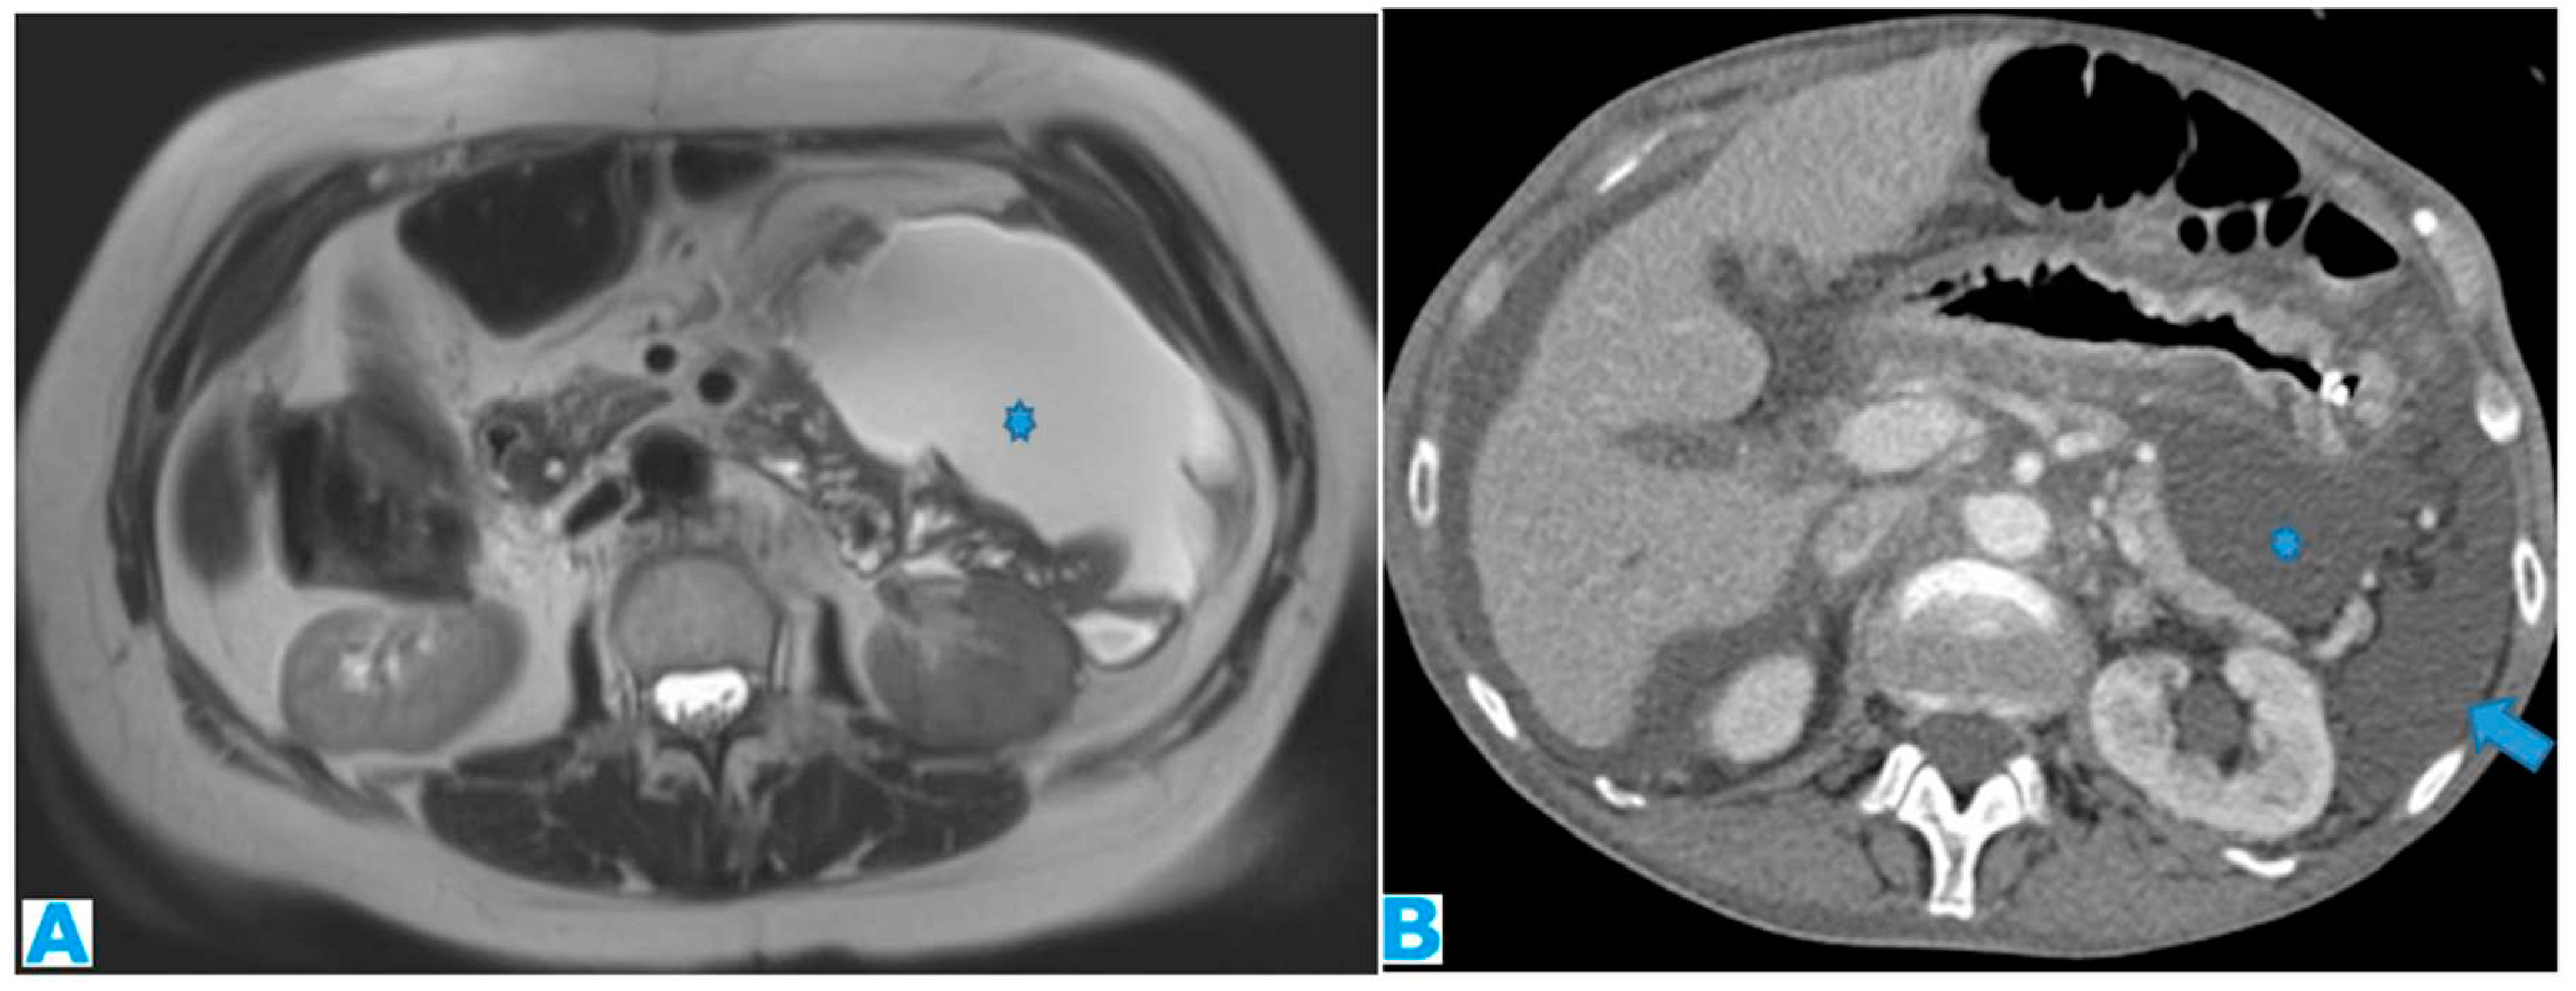

Figure 23.

Axial CE-CT. PC from ovarian carcinoma: mesenteric seeding. Mesenteric involvement may happen as a combination of deposits involving both the mesentery and the bowel serosa, as in this case. Observe the clustered SB loops appearance. The calcified content of some of the deposits enhances their presence (arrow). Omental deposits (*).